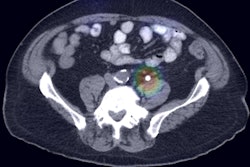

With the power of deep learning, computers can see things humans can't or can't reliably detect such as genomic markers, according to Erickson.

"These are the sorts of things that computers can do that are quantitative and can add significant value to the management of patients," he said. "And this is where computers clearly are able to surpass humans."

Erickson also referred to Siegel's challenge from a few years ago: that he would wash the car of the first software developer to create a program that finds the adrenal glands more consistently than an 8-year-old child taught to do so in less than 15 minutes. A team from the U.S. National Institutes of Health (NIH) recently was able to perform that task, producing Dice coefficients -- a statistical measure of similarity -- of around 65% to 80% as of November 2016.

While acknowledging the historically impressive achievement from Dr. Ronald Summers, PhD, and his team from the NIH, Siegel said the Dice coefficients suggested overlap with the correct answer was only around 65% to 68%. A fifth grader with 15 minutes of training would exceed that performance, Siegel said.

"And so if we can't even find the adrenals, then how are we going to essentially replace radiologists and do the things that need to be done?" he asked. "If I can't even find the adrenals, how can I identify an adrenal mass and determine how it enhances, etc. I can't even begin to do the job of the radiologist if I can't even find [the adrenals]."